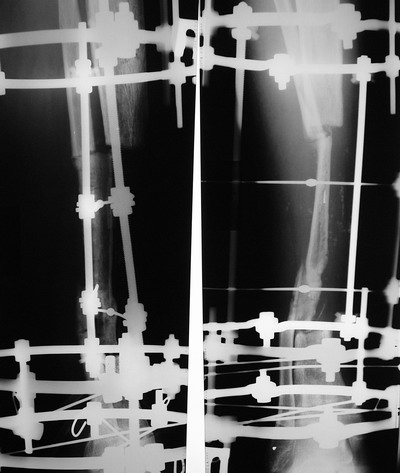

> Пациент Г.,мужчина 56 лет, Хронический посттравматический остеомиелит

> костей левой голени. *Свищевая форма( Свищ в обдасти дистального

> фрагмента по передней поверхности).* Латентное течение. Дефект

> большеберцовой кости в с/з 8 см....

Владимир, свободная костная пластика на фоне свища вряд ли оправдана. Почему

не рассматриваете вариант транспорта кости по Илизарову? Что собираетесь

антибиотиками, бусах. После купирования инфекции переходить к замещению

дефекта: за счет удлинения концов б\б кости или тибиализации м\б. На

начальном этапе фиксация только в аппарате, в последствие для удержания

достигнутого можно перейти на фиксацию интрамедуллярным штифтом (см.

вложенные файлы)